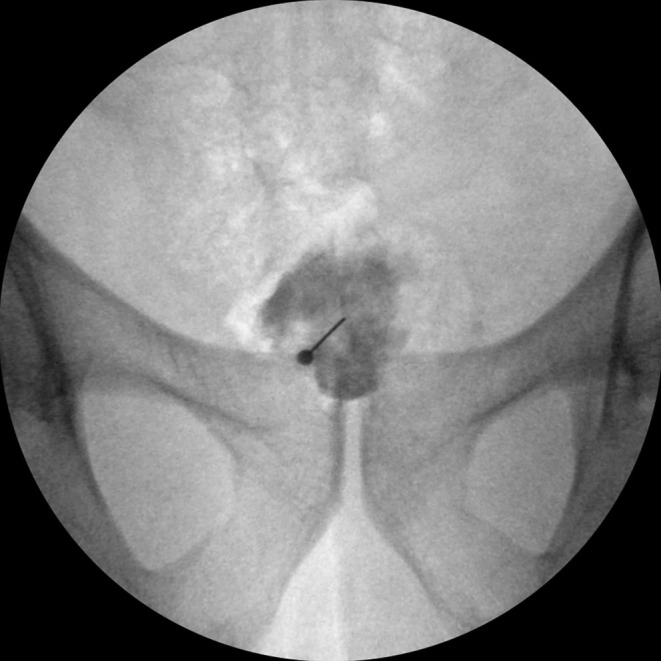

Abstract Image